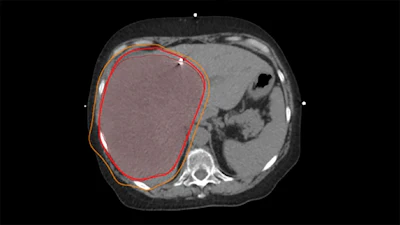

Sample radiation treatment plan demonstrating a "supermassive" right liver tumor with planned radiation "isodose lines" shown in bright red and orange.The University of Texas MD Anderson Cancer Center